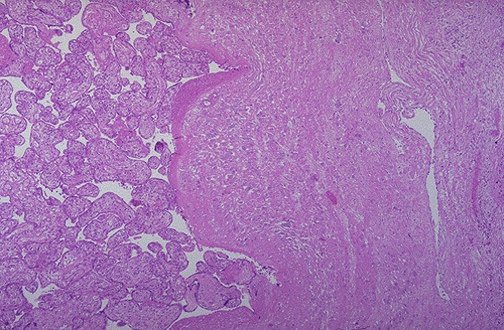

| Microscopically, the placental villi interdigitate directly with the uterine myometrium, without an intervening decidual plate. This is placenta accreta, which will result in lack of normal separation at delivery, leading to marked hemorrhage necessitating emergency hysterectomy. The classification of placental invasion into myometrium is as follows: |

| Type | Invasion of chorionic villi has occurred |

| Accreta | Superficially into myometrium |

| Increta | Deep into myometrium |

| Percreta | Through the myometrium |